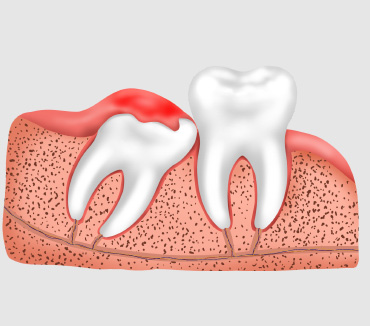

什么是阻生智齿?

阻生牙是指部分萌出或完全不能萌出,且以后也不会自行萌出的牙,这种萌出异常是由邻牙、骨或软组织的阻碍引起的。其中阻生第三磨牙也叫做阻生智齿。

阻生智齿的危害

阻生智齿会影响人们的正常咀嚼功能,而且容易引发炎症感染,所以在出现智齿阻生牙之后要及时拔除治疗。

什么是智齿发炎?

智齿发炎即智齿冠周炎,智齿冠周炎是一种发生在第三磨牙周围软组织的炎症。智齿冠周炎通常是由于智齿萌出不足、细菌感染等原因引起。

智齿发炎的危害

智齿周围牙龈炎、牙周炎和牙槽骨吸收;颌骨骨髓炎疗程长且治疗困难;周围软组织、牙齿损伤;口腔系统破坏,引发严重后果。